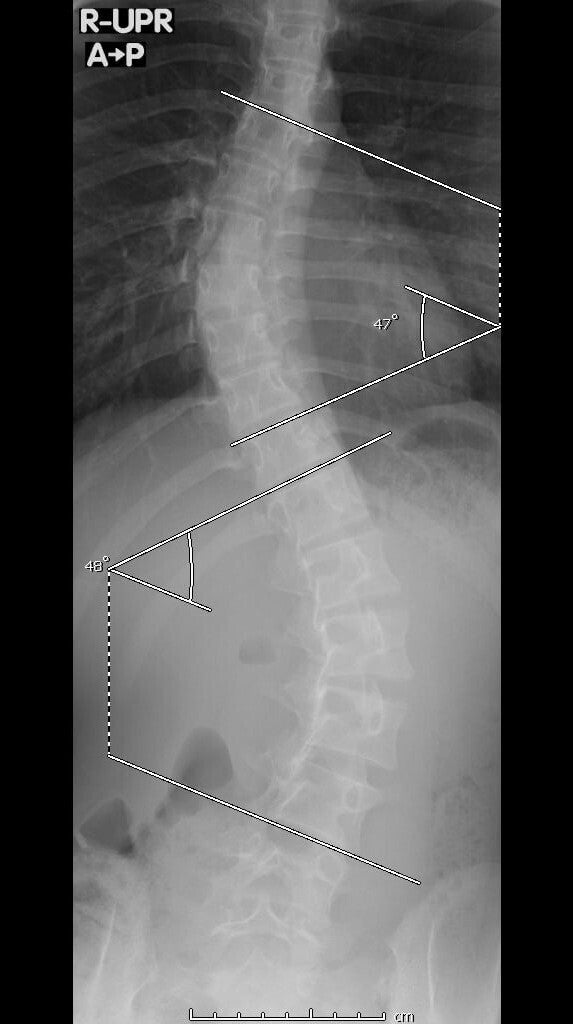

私はカンボジアに住んでいた時に偶然家族によって重度特発性側弯症が発見されました。ですが、矯正器具と理学療法のおかげで今後手術が不要なレベルまで改善しました。私も実際に側弯症と診断されてから知ったのですが、思春期特発性側弯症という病気は思春期の子供たちの100人に2、3人発症するそうです。そして、特発性側弯症の発症原因はいまだ不明です。悪化するとひどい腰背部痛や、重度の場合には内臓の圧迫によって呼吸困難や心不全にも陥り、発見が遅いと侵襲性の高い手術をするしかありません。日本には学校検診の中に、側弯症検診というものがありますが、私の住んでいたカンボジアでは学校検診さえもなく、私の側弯症の発見も遅れてしまいました。